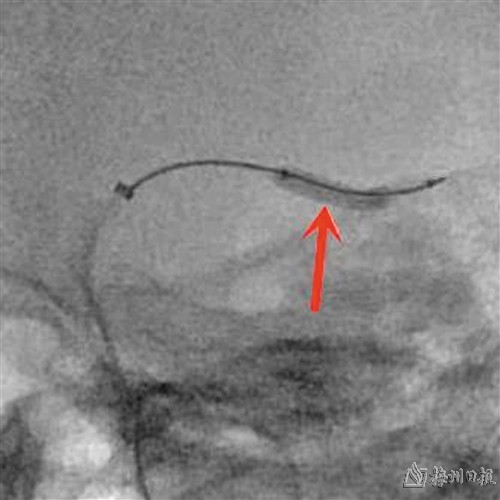

术中球囊扩张。(医院供图)

市人民医院神经内一科主任李水彬介绍,患者存在高血压病3级(极高危)、2型糖尿病、痛风等多种基础疾病,手术风险相对较高。综合评估后决定采用新型导管Fastunnel®输送型球囊扩张导管为患者实施微创介入治疗,这是国内首款输送型球囊扩张导管,采用“球囊+微导管”一体化设计,具有“一体双能”作用,一次完成球囊预扩张、支架释放、球囊后扩张全过程。相比传统手术减少了多次器械交换步骤,简化了术中操作,提高了手术安全性。手术历时1小时顺利完成,较常规手术缩短了一半时间。